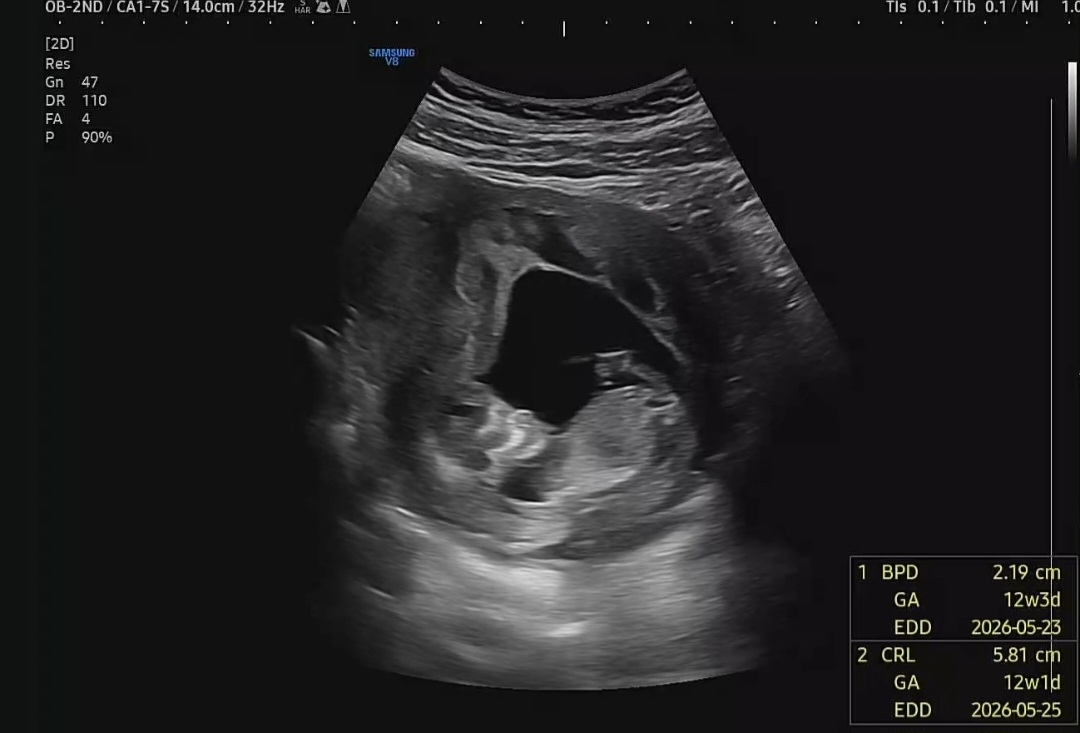

12주 3일차입니다(성별 한번 봐주세요~)

12주 3일차입니다 다음 초음파가 4주나 남아서, 조급한 마음에 투표한번 올려봅니다 이렇게 올려도 식별이 가능한지 조차 잘 모르지만 잘 부탁드립니다 ^^